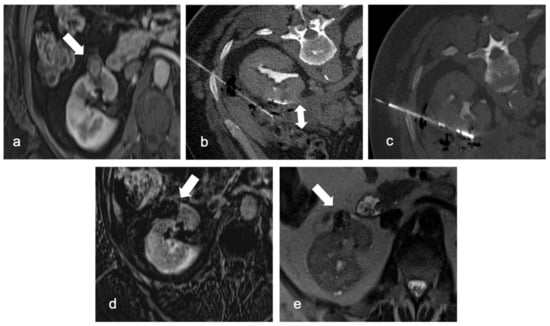

Damage to nearby organs can occur as well: for example, if the renal mass is too close to the bowel, hydro-dissection (Figure 3) (for instance, injecting a glucose solution) could be a strategy to widen the space between the lesion and the organ and minimize possible lesions.

Figure 3.

Arterial phase MRI shows a contrast enhancing anterior right kidney mass (arrow) in a 63-year-old man (a). Due to renal mass proximity to hepatic colon flexure, hydrodissection is obtained with 500 mL of glucose solution (double arrow, (b)). RFA is then performed with margin of safety between the probe and the colon (c). A follow-up MRI 2 months later revealed the necrotic mass (arrows) with no evidence of residual or recurrent tumor in the ablation zone: digital subtraction contrast-enhanced MRI (d) and T2w sequence (e).